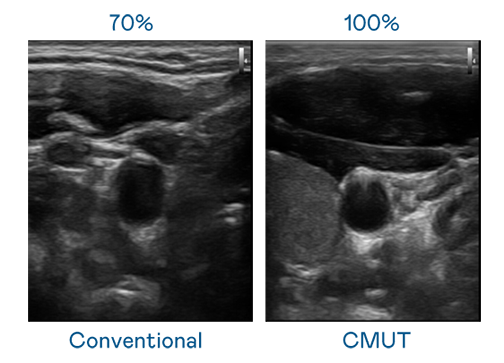

CMUT 技術是一種用電容式微機電元件來產生超音波訊號的技術。與傳統 PZT 壓電式技術相比,CMUT 頻寬增加 30%,更寬頻的超音波訊號讓影像解析度大幅提升,是實現高影像品質醫療超音波掃描、促進精準醫療發展的關鍵技術。

超音波影像的解析度高低,首先取決於探頭能發出的訊號頻寬。爱游戏 CMUT 可提供高清晰的超音波訊號,提供高頻寬、高靈敏度、影像紋理細節更高的超音波影像,協助醫護人員縮短影像判讀時間及利用精準的醫療影像進行診斷。